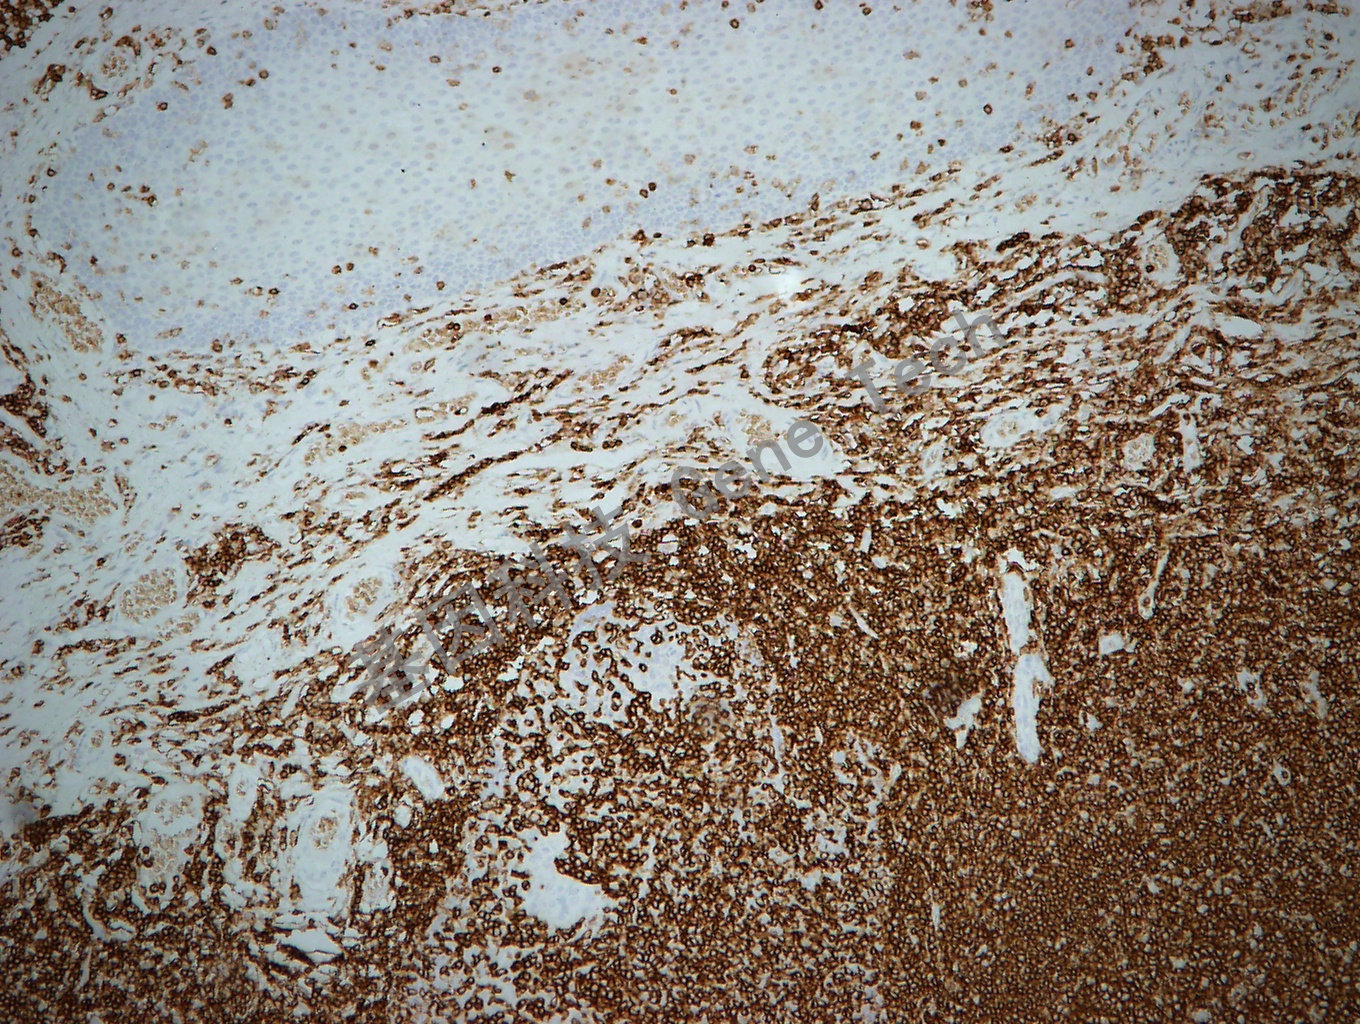

扁桃体石蜡切片(10X),用 CD45RB(GT2219)染色,细胞膜阳性,DAB 显色

扁桃体石蜡切片(40X),用 CD45RB(GT2219)染色,细胞膜阳性,DAB 显色